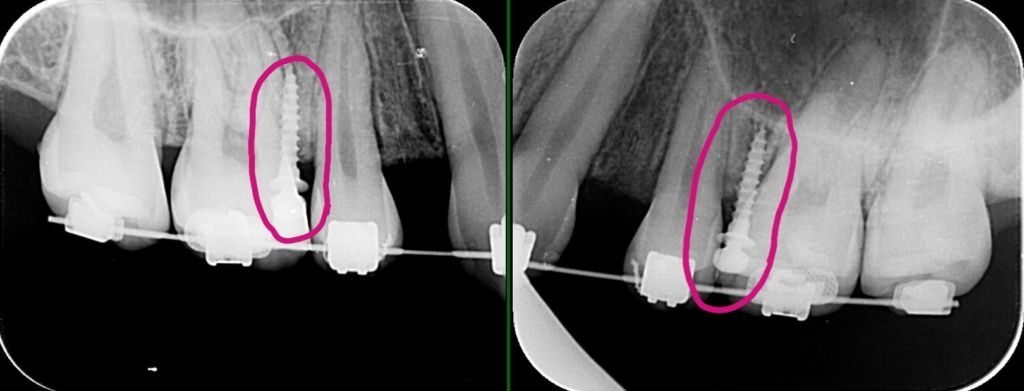

レントゲン写真で確認すると、

この患者さんの場合、

【アンカースクリューの植立】

治癒期間を待ったうえで、前歯を積極的に引っ込めながら、残る抜歯スペースを閉じます。

レントゲン写真でも矯正治療前後を比較してみましょう

レントゲンで見ると、治療前後で口元の変化は小さいように見えますが・・・